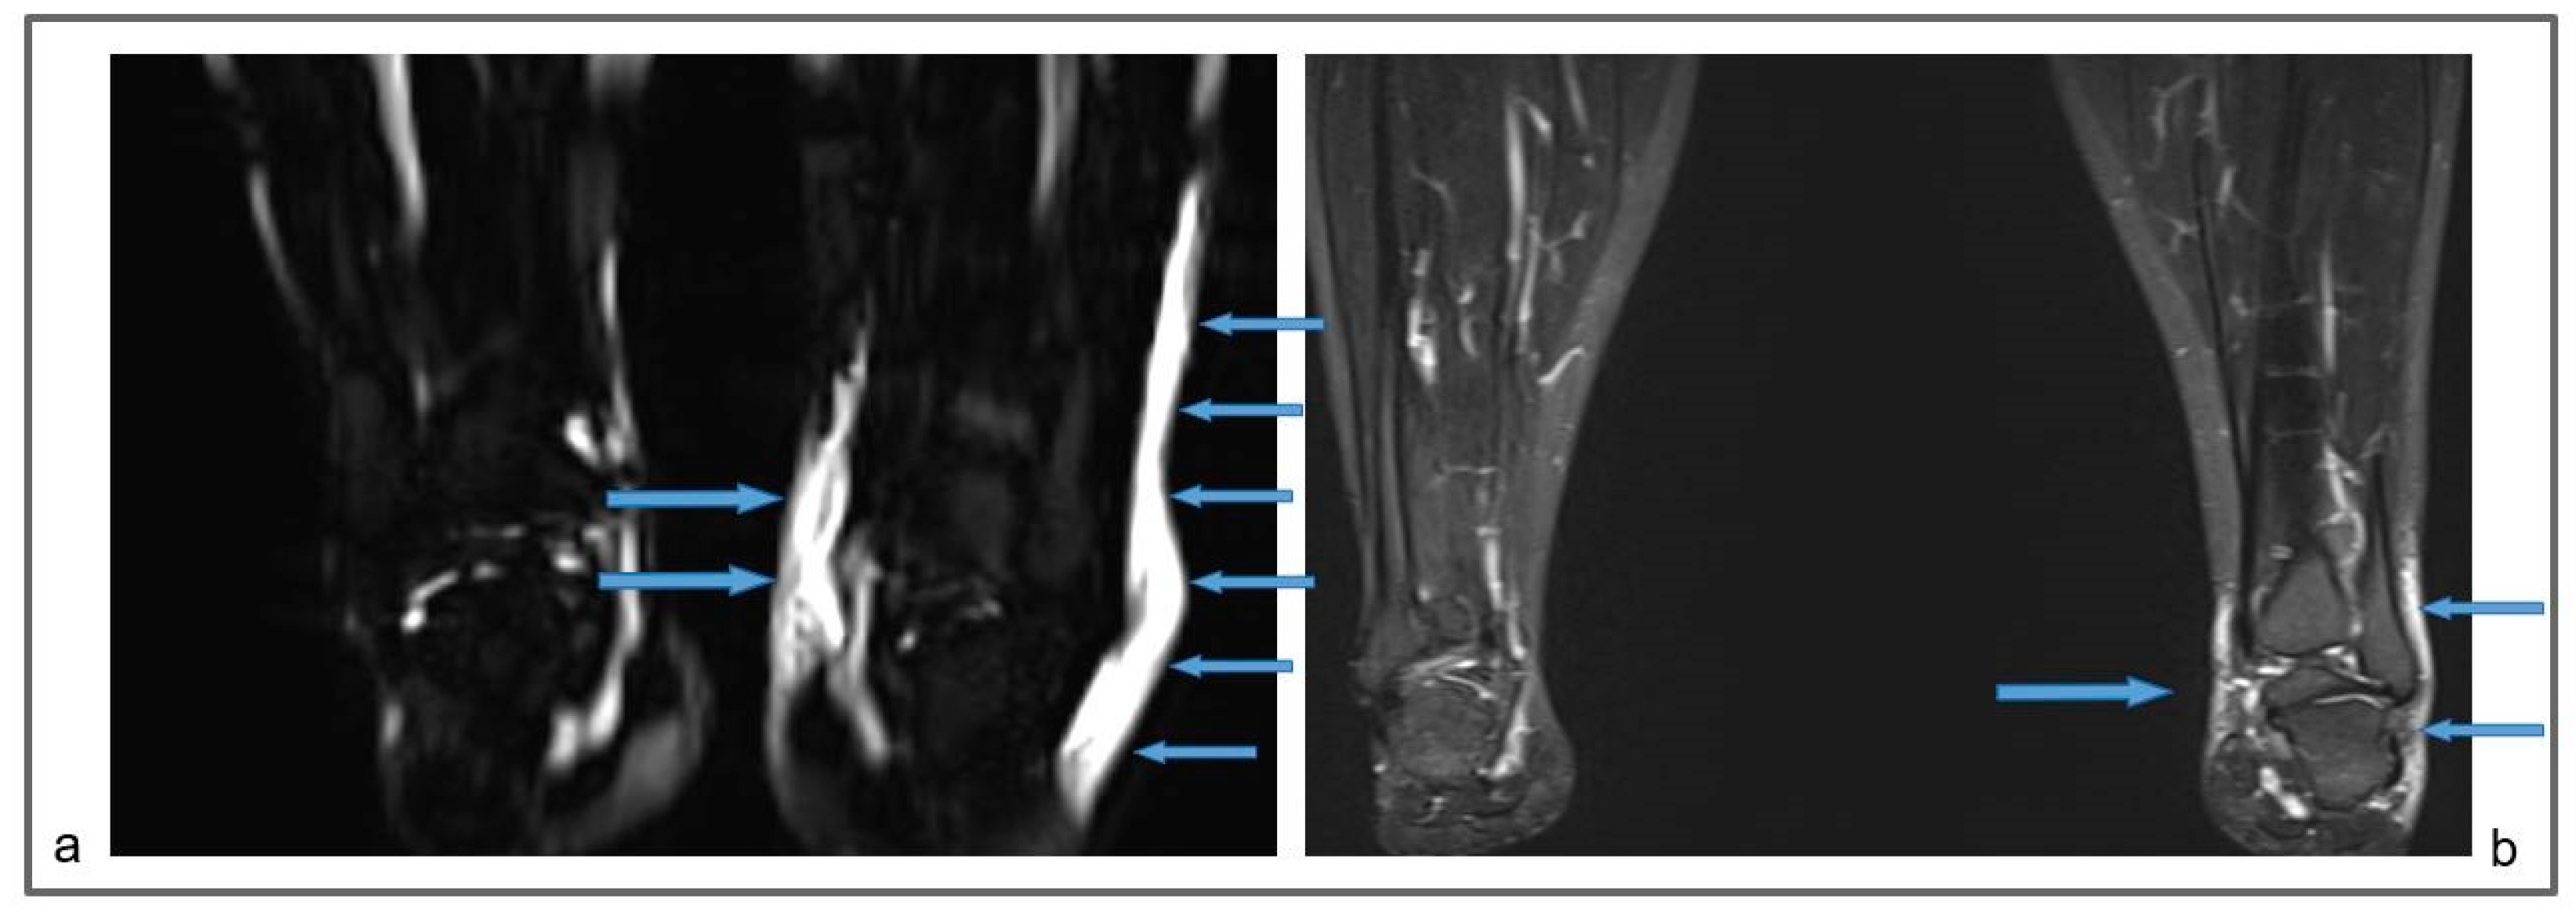

Figure 6.

Patient 3: Preoperative non-contrast MR lymphography (a) and at 1-year follow-up (b), based on high-resolution, heavily T2-weighted coronal sequences (turbo spin echo with repetition time 2870 ms, echo time 797 ms, field of view 380 × 380 mm, matrix 358 × 384, slice thickness 1 mm). The patient suffered from a marked increase in the size of the left ankle and distal leg, due to a large amount of epifascial fluid (a; blue arrows). The follow-up demonstrates a marked reduction in the epifascial fluid with a significant size reduction of the affected areas (b; blue arrows).

Figure 7.

Patient 3: Follow-up MR lymphography showing lymph nodes transplanted in the popliteal fossa (blue arrows) and coronal reconstruction of a 3D short-time inversion recovery (STIR) with repetition time 3000 ms, echo time 254 ms, inversion time 160 m, field of view 460 × 504 mm, matrix 315 × 384, slice thickness 1 mm.

Figure 8.

Patient 3. (a) Preoperative non-contrast MR lymphography (a) (based on high-resolution heavily T2-weighted coronal sequences (turbo spin echo with repetition time 2870 ms, echo time 797 ms, field of view 380 × 380 mm, matrix 358 × 384, slice thickness 1 mm) and follow-up non-contrast MR lymphography (b,c) 1 year post-surgery. Follow-up (b,c) imaging shows the presence of new lymphatic vessels (blue arrows), not recognizable at the preoperative exam (a).